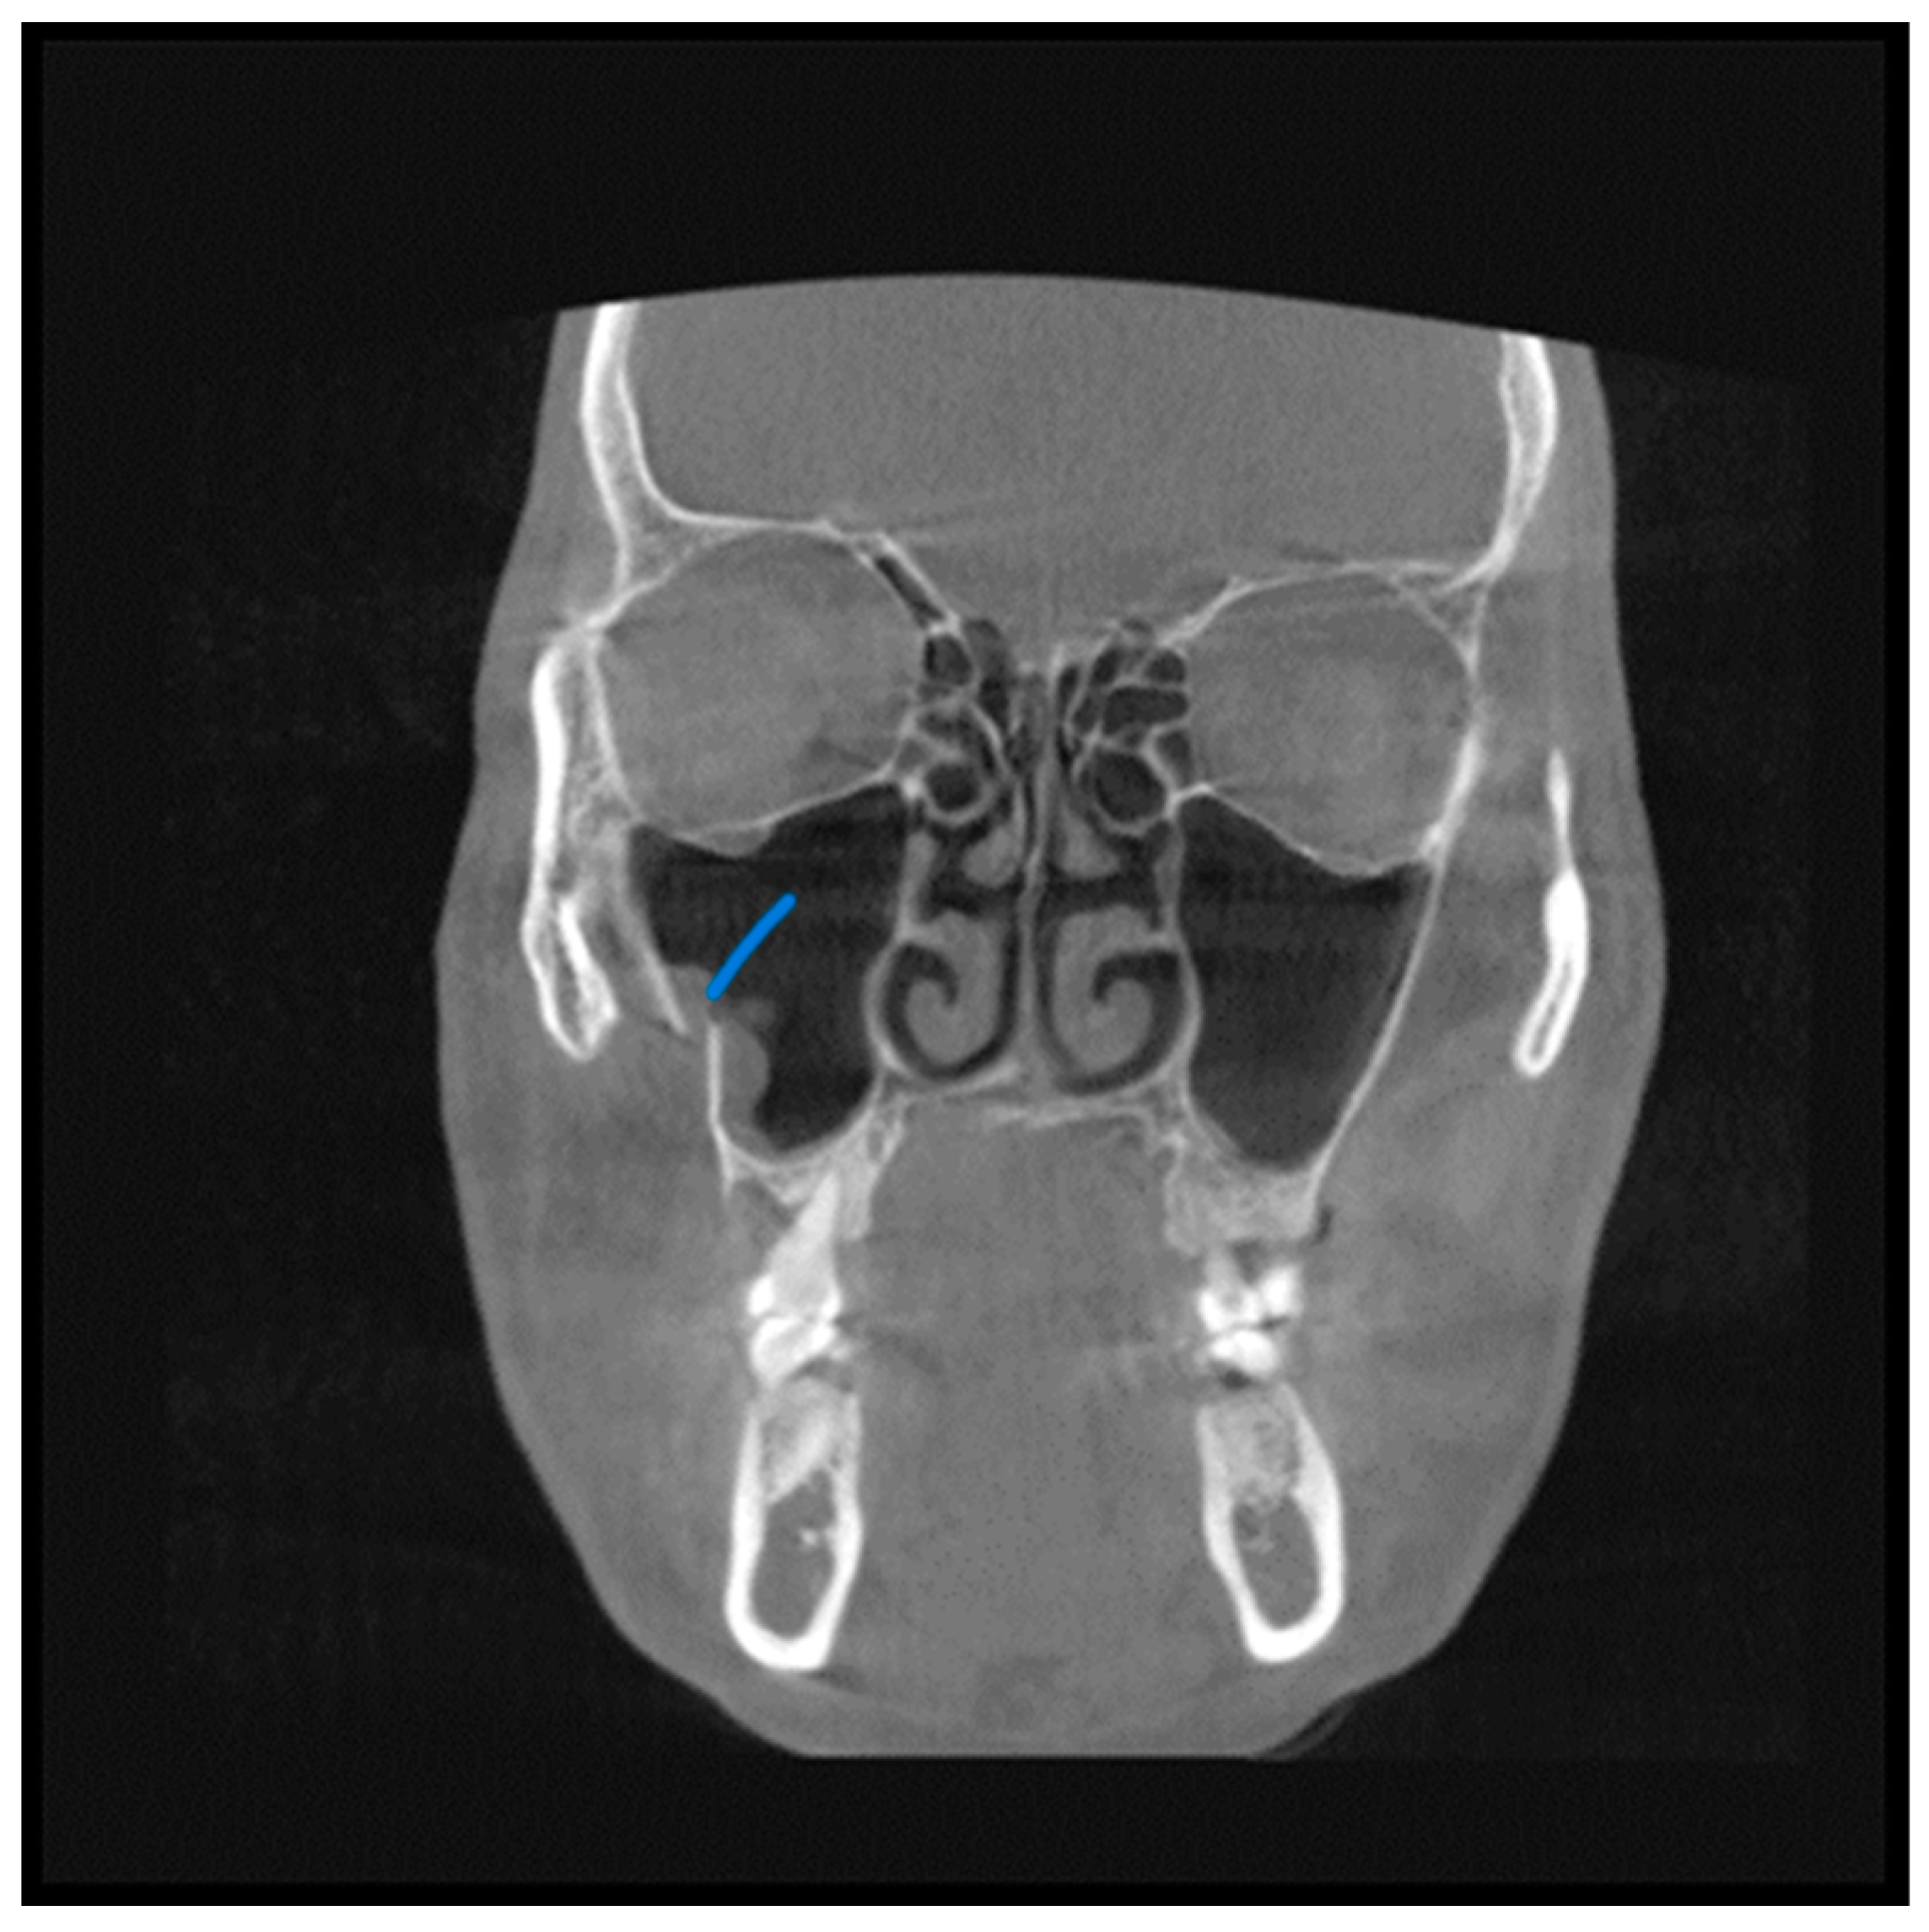

- Partial or complete opacification of the sinus cavity;

- Fracture lines.